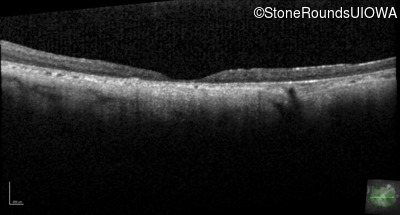

Optical Coherence Tomography - Right - 10/225 sc

Exemplar / OCT Stack

OCT Stack